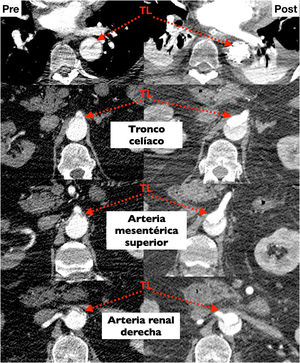

Probablemente la única situación en la que sea imprescindible para salvar la vida del paciente es cuando la falsa luz esté rota a nivel del arco, situación poco frecuente (figs. 1 y 2). Más frecuente es la presencia de malperfusión cerebral estática (por disección de uno o varios de los troncos supraaórticos, con oclusión de la luz verdadera) o de malperfusión visceral dinámica (por colapso de la luz verdadera, generalmente por reentradas en el arco o en la aorta descendente proximal). En estas dos circunstancias, aunque no es mandatorio, la sustitución del arco aórtico sí es la manera más eficaz de corregir la malperfusión20 (figs. 3 y 4).

Planificación preoperatoria. La tomografía axial computarizada (TAC)Un aspecto fundamental es dedicar un tiempo al análisis detallado de la angioTAC preoperatoria. Tenemos que decidir la estrategia de canulación y de protección cerebral, la zona de anastomosis distal, identificar la luz verdadera, la localización de la rotura intimal, las reentradas, la afectación o no de los troncos supraaórticos y valorar el riesgo de malperfusión, entre otros. Con respecto al tamaño de la prótesis a implantar, hay diversas formas de calcular el diámetro del stent a implantar (diámetro total, área de la luz verdadera…), pero el aspecto más importante es evitar su sobredimensionamiento, ya que puede causar nuevas reentradas (desgarro intimal distal inducido por el stent [dSINE]) y producir malperfusión visceral en el postoperatorio inmediato o remodelado negativo de la luz falsa en el seguimiento43-45.